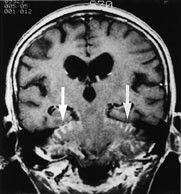

Durale metastaser fremtrer som kurvilineære streker med patologisk signaløkning etter kontrast. Disse strekene skal følge skalletakets innside og ikke gå inn i sulci på hjernens overflate (fig 9). Signaløkningen kan være segmental eller følge skalletaket i hele omkretsen. Segmental signaløkning skal være til stede på flere nærliggende snitt. Atskillelsen mot den lette fysiologiske kontrastoppladning i dura kan være vanskelig. Durale metastaser kan også ha et fokalt preg.

Leptomeningeal tumor fremtrer som tynne streker med kontrastoppladning som følger gyri dypt inn i sulci (fig 10), eventuelt som små knuter på hjernens overflate eller et tynt lag med patologisk kontrast utenpå hjernestamme eller hjernenerver. Ettersom arachnoidea ligger tett inntil det indre laget av dura, kan dural-araknoidal tumor ikke med sikkerhet skilles fra pial-subaraknoidal tumor. Påvisning av en dural-araknoidal patologisk signaløkning utelukker dermed ikke samtidig forekomst av tumor i pia eller subaraknoidalrom.

Hydrocephalus kan være uttrykk for at resorpsjonen av cerebrospinalvæske på overflaten er redusert som følge av diffus tumorutsæd i pia (fig 10).